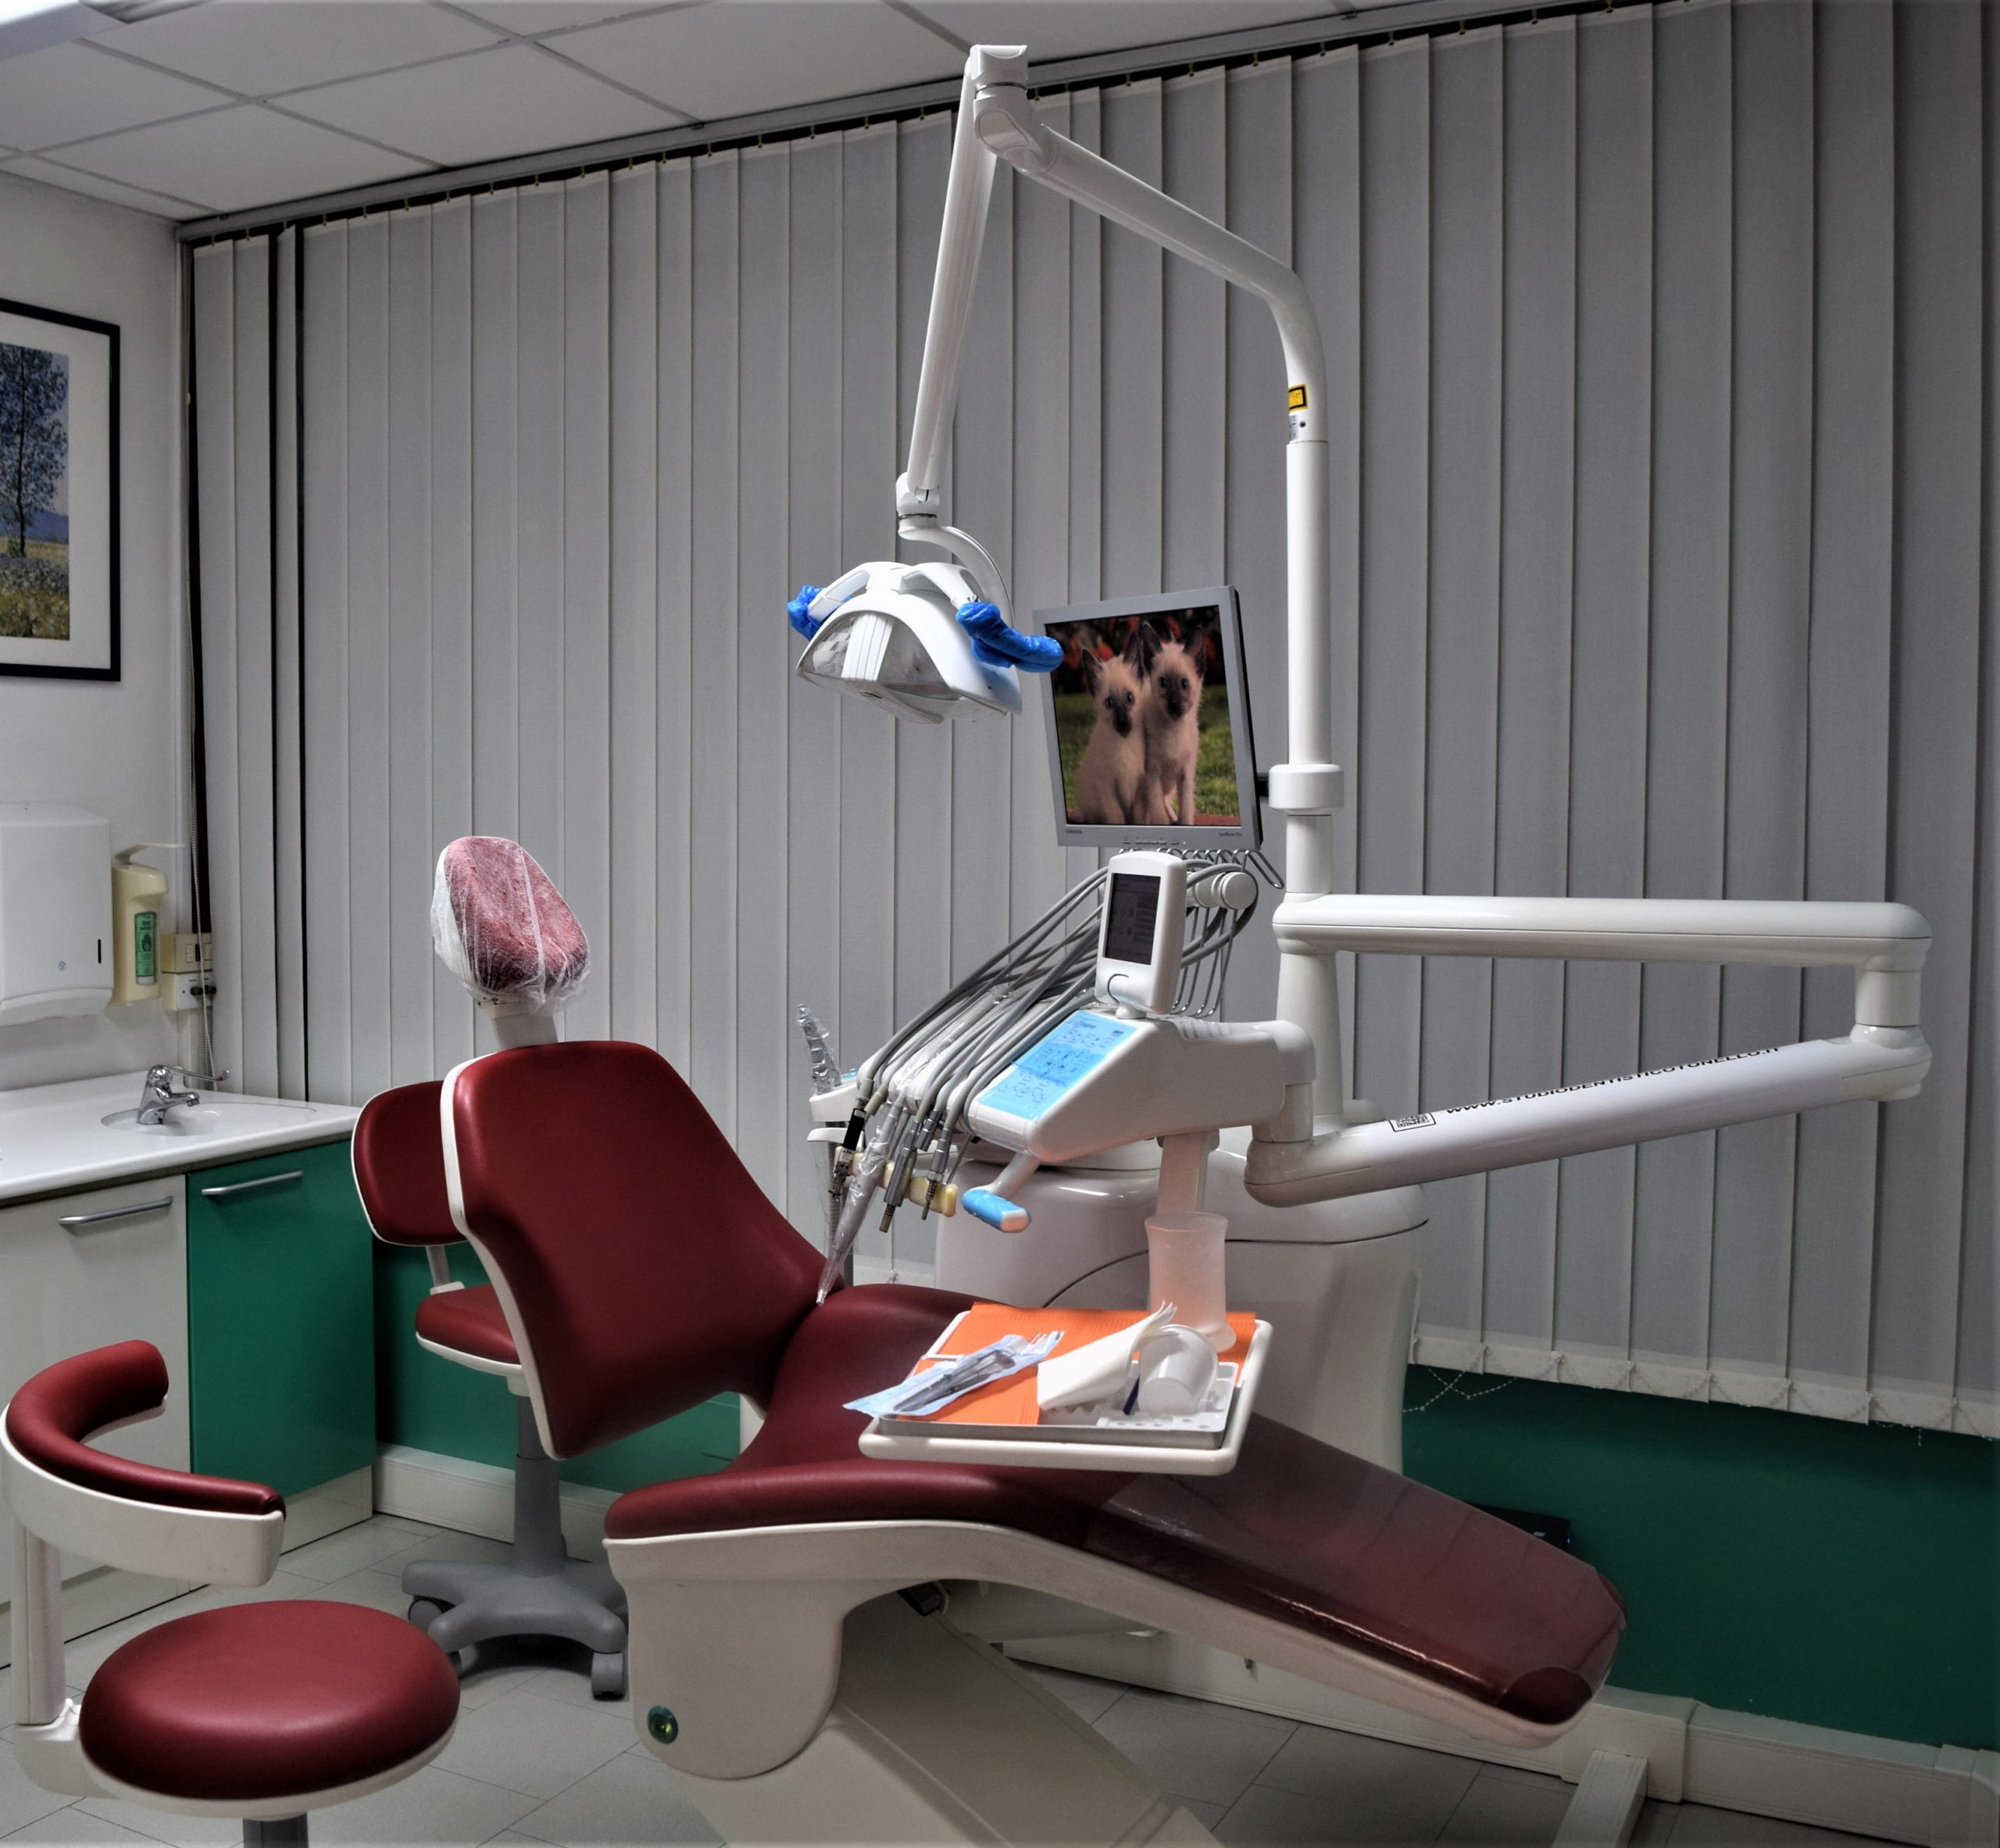

IN COSA CONSISTE UN INTERVENTO ENDODONTICO

Il trattamento endodontico prevede la rimozione fino alle radici del dente della polpa danneggiata e nella sua sostituzione con un’otturazione permanente. In questo modo vengono elimitai tutti i batteri che si erano accumolati e che hanno causato il danno e il dente una volta riparato potrà tornare a svolgere la sua funzione.

Il trattamento prevede l’utilizzo dell’anestesia locale per neutralizzare il dolore e tenerlo sotto controllo, a seguito della terapia nelle ore successive è possibile sentire un indolezimento più o meno persistente che può essere controllato grazie all’assunzione di analgesici.